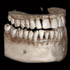

Höchste Bildqualität

X-ERA SMART verfügt über ein einzigartiges Patientenpositionierungssystem im 3D Bereich, das jede Bildverzerrung durch Patientenbewegung komplett ausschließt. Das Technologiekonzept erzeugt eine Bildqualität in extrem hoher Auflösung. Zwei verschiedene Aufnahmegrößen mit einer Voxel Größe von 80μm / 100 μm liefern in jeder Sichtfeldgröße (FoV) exzellente Ergebnisse für die weitere Diagnostik und Behandlung.

Nacholgend ein paar phänomenale Bilder & Werte,

die nicht nur einem Fachmann die Sprache verschlagen:

Aufnahmeparameter: Ceph LA; 82 kV; 10 mA; 8.0 s; 0.8 mm CU + 6.0 mm AL

gemessene Dosis: 2.99 µGy